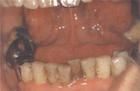

頦下間隙感染是指頦下間隙急性化膿性感染,主要臨床表現有淋巴結腫大、頦下三角區皮膚充血、疼痛有等。

基本簡介 症狀體徵 臨床表現 病理生理 診斷檢查什麼是頜下間隙感染?頜下間隙感染是指頜下間隙急性化膿性感染,主要臨床表現有頜下區豐滿,淋巴結腫大、壓痛。頜下間隙感染是怎么回事?頜下間隙形成膿腫時範圍較...